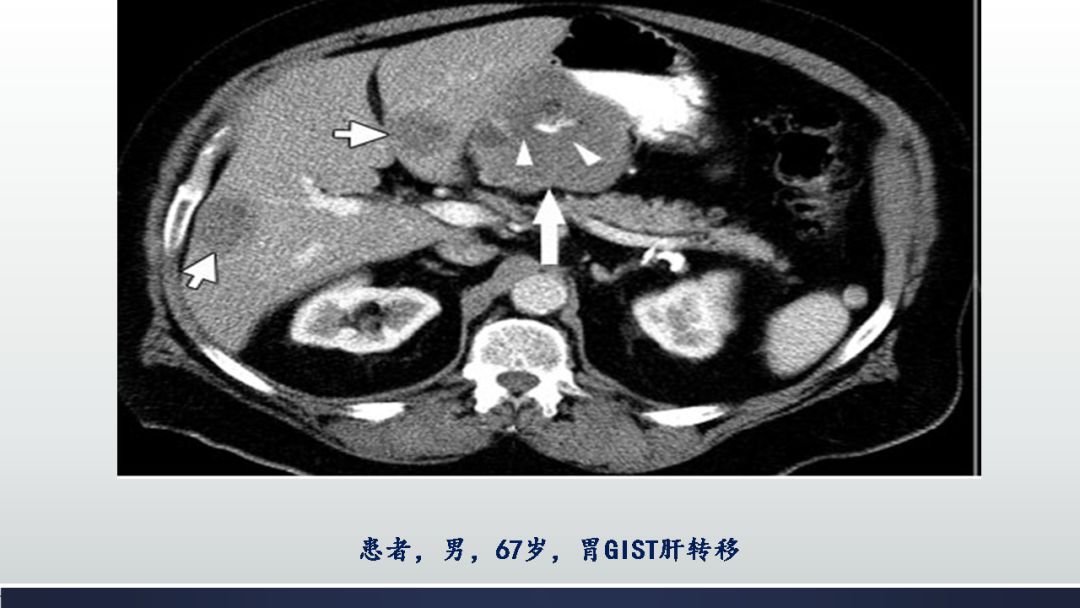

胃肠道间质瘤的ct诊断丨影像天地

图片尺寸960x720

胃肠道间质瘤(gist)影像表现_肿瘤

图片尺寸1080x608